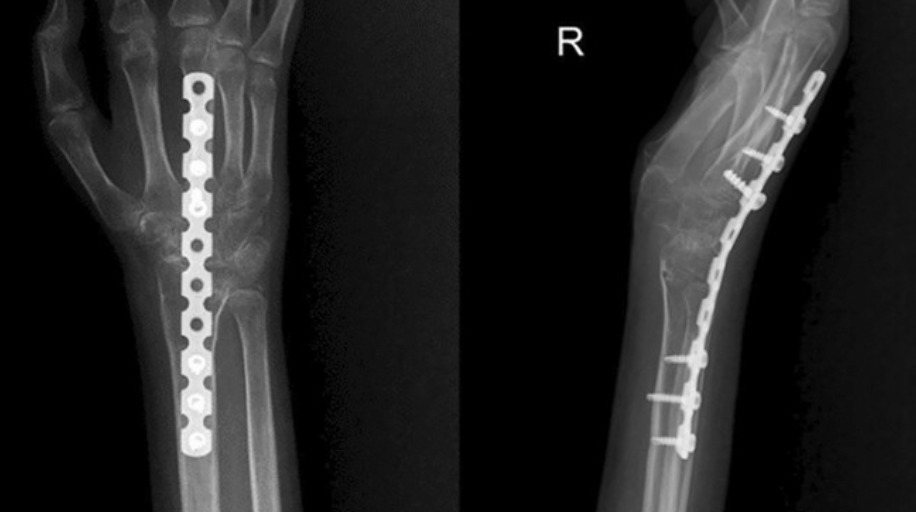

- Total wrist arthrodesis: Fusion of the entire wrist to the radius. Eliminates pain completely. Trading motion for pain relief — appropriate for end-stage pancarpal arthritis, failed partial fusion, or wrist with poor bone stock. Retains forearm rotation (pronation/supination).